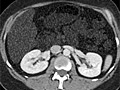

A computed tomography (CT) scan uses X-rays to make detailed pictures of structures inside of the body.

During the test, you will lie on a table that is attached to the CT scanner, which is a large doughnut-shaped machine. The CT scanner sends X-rays through the body area being studied. Each rotation of the scanner provides a picture of a thin slice of the organ or area. All of the pictures are saved as a group on a computer. They also can be printed.

A CT scan can be used to study all parts of your body, such as the chest, belly, pelvis, or an arm or leg. It can take pictures of body organs, such as the liver, pancreas, intestines, kidneys, bladder, adrenal glands, lungs, and heart. It also can study blood vessels, bones, and the spinal cord.